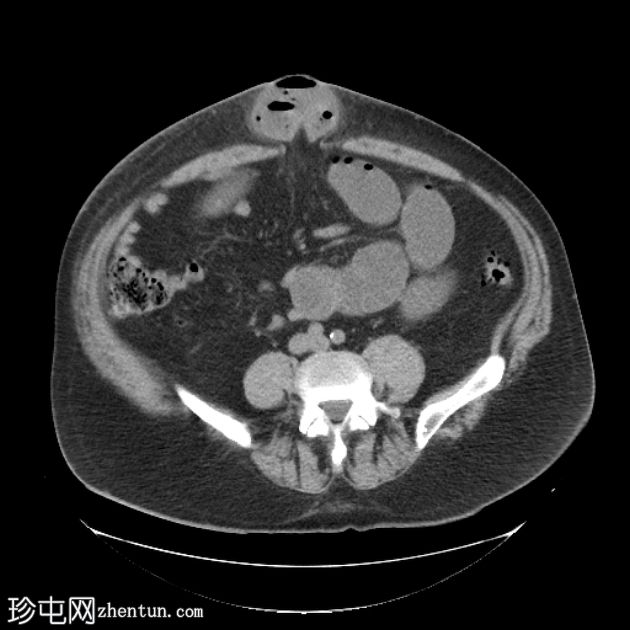

轴位

平扫

多处扩张的小肠袢内可见多个气液平面,直至进入脐疝的肠袢处可见移行点,而从疝口出来的远端小肠袢则呈塌陷状态。

诊断:嵌顿性脐疝继发急性小肠梗阻。